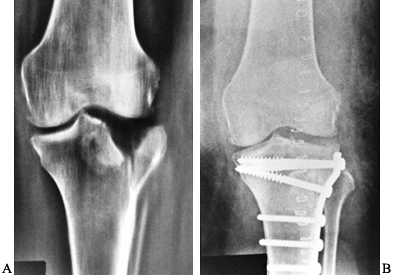

less than 5 mm of depression and are stable on examination can be

brace for protection. Patients with displaced fractures of more than 8

reduction and internal fixation (66) (Fig. 131.11).

![]() |

Figure 131.11. A: Tibial plateau fracture. B: Fixation of tibial plateau fracture.